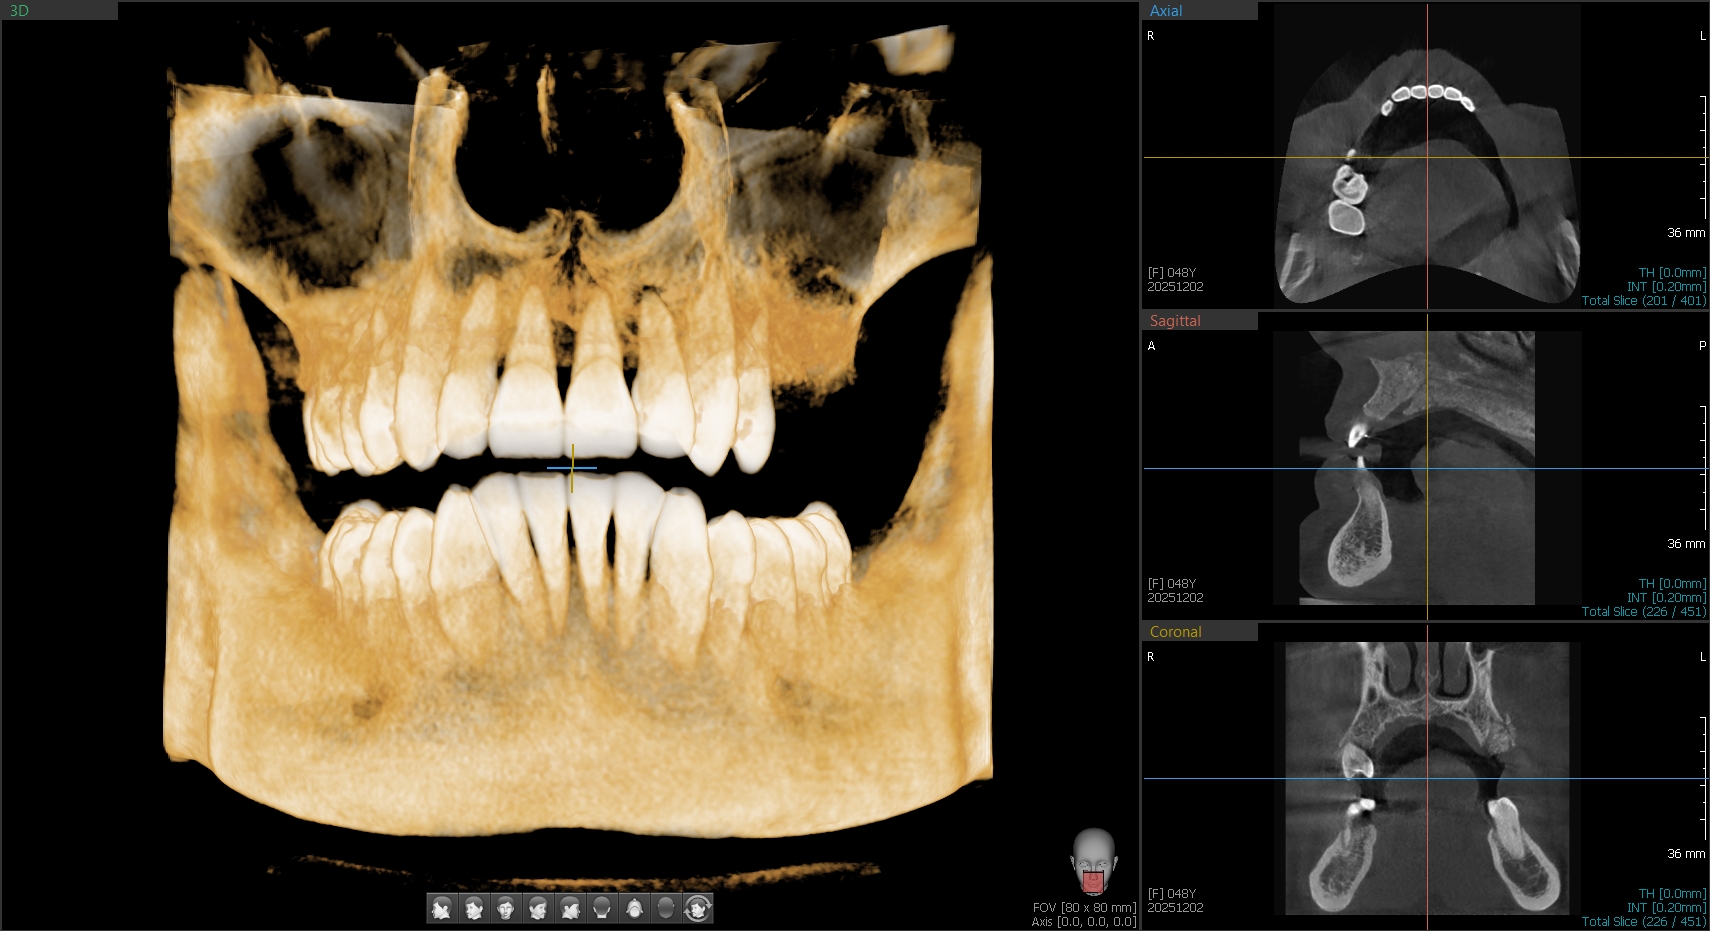

3D CBCT

прецизни 3D изследвания за импланти и сложни случаи.